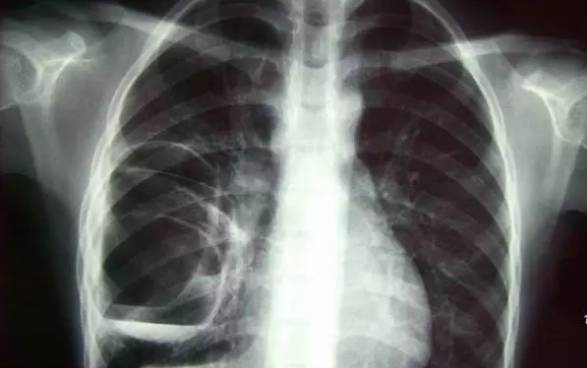

胸部——先看DR,细看CT

DR可粗略检查肺、心影、主动脉弓、肋骨等,可以检查有无肺纹理增多、肺内较大肿块、主动脉结钙化等。胸部CT检查显示出的结构更清晰,对胸部病变检出敏感性和准确性均优于常规X光胸片,特别是对于筛查早期肺癌有重大意义。